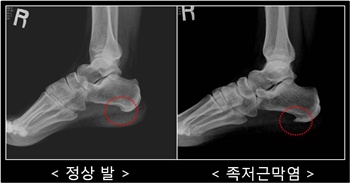

족저근막은 발뒤꿈치 뼈에서 시작해 앞 발가락 뼈에 부착된 질기고 단단한 막을 말하는데, 발바닥의 스프링 역할을 하여 충격을 흡수하거나 아치(발바닥의 움푹 파인 부분)를 받쳐주어 발바닥을 보호하는 역할을 한다. 이러한 기능을 하는 족저근막이 무리한 발바닥 사용이나 과로로 인해 염증이 생기거나 붓게 되는 것을 족저근막염이라 한다.

족저근막염은 초음파, MRI 등을 이용해 족저근막의 두께를 측정, 그 여부를 판단한다. 질환 초기에는 1~2주 정도 안정을 취하게 되고 소염 진통제를 복용하며 스트레칭 등으로 치료할 수 있다. 증상이 심한 경우에는 수술이 권해지지만 최근에는 굳이 수술을 하지 않더라도 치료할 수 있는 체외충격파와 PRP주사요법이 각광받고 있다.